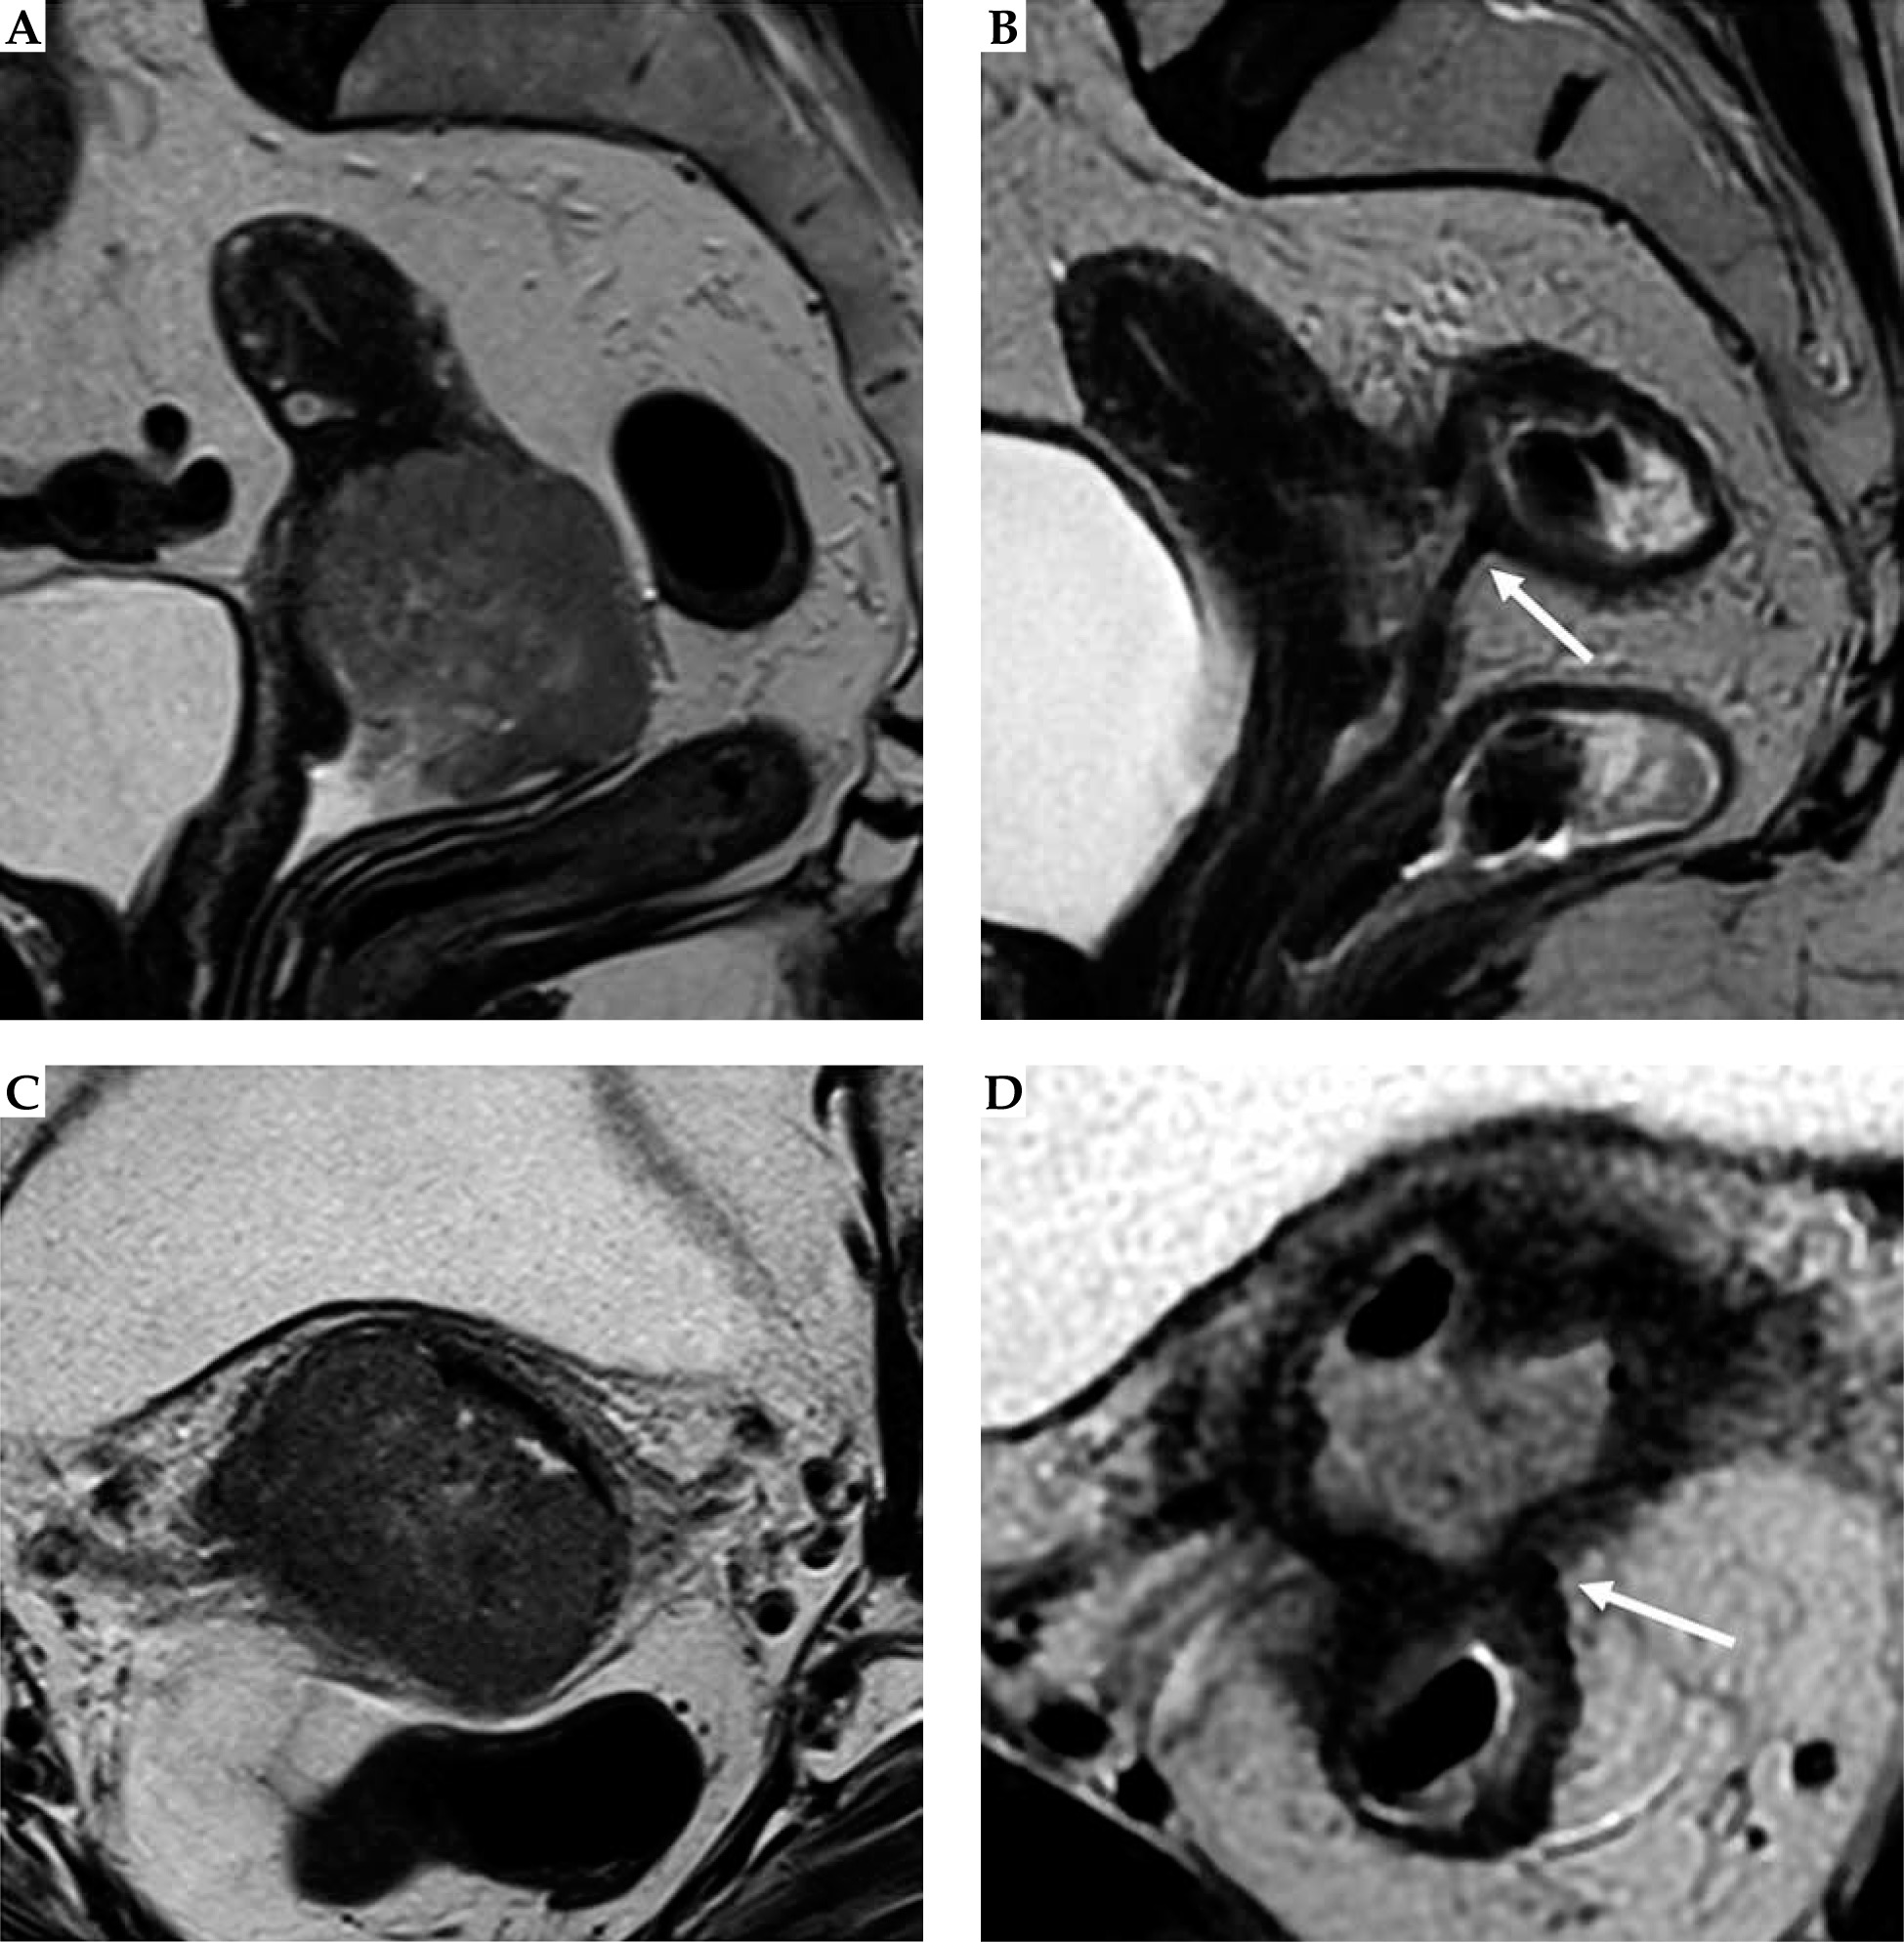

Fig. 3

Post-external beam radiotherapy (EBRT) recto-vaginal fistula. Baseline and post-EBRT MRI in 72-year-old woman with squamous cervical carcinoma. At baseline MRI (A, C), T2-w sequences show the hyperintense cervical mass, extending to the upper third of the vagina, with maximum diameter of 50 mm (any plane). After concurrent EBRT (B, D), T2-w sequences show the presence of an hyperintense area in the posterior wall of the cervix and posterior vaginal fornix. Post-EBRT MRI presents a rectovaginal fistula (arrow)